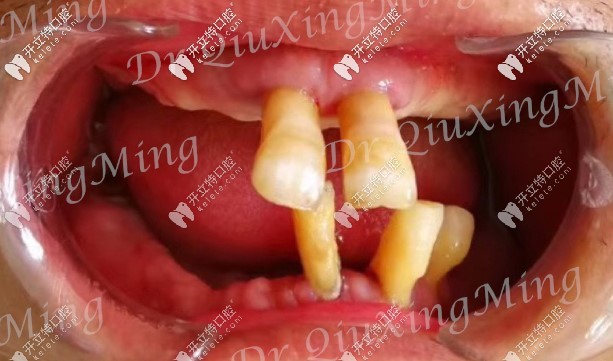

首先看下他的牙齒情況:嘴里還剩下5顆牙,還有2顆殘根,邱醫(yī)生建議全部拔掉,因?yàn)槟?顆牙也已經(jīng)松動(dòng)了,沒有保留的必要。

大爺口腔剩余牙齒圖